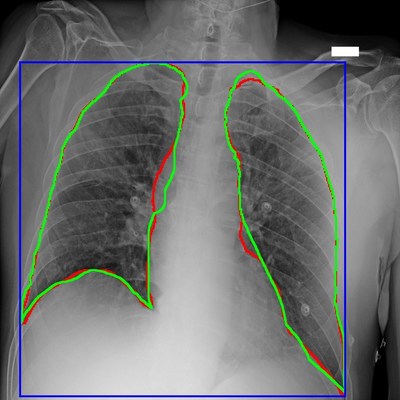

The “AIforCOVID” Imaging Archive is a shared collection of images and clinical data for developing innovative Artificial Intelligence-based methods to predict clinical developments of SARS-CoV-2-related disease. This valuable tool enables the international scientific community to share radiological and clinical data and find innovative solutions to combat the disease. The “AIforCOVID” Imaging Archive, which is available, open access to the global scientific community at https://aiforcovid.radiomica.it/, contains more than a thousand positive patient chest radiographic examinations carried out upon hospitalization. Each X-ray is associated with clinical information about the patient collected at that time.

The Istituto Italiano di Tecnologia (IIT) of Genoa and Università Campus Bio-medico of Rome were responsible for data analysis and developed the artificial intelligence algorithms, working in partnership with the Centro Diagnostico Italiano and Bracco Imaging teams. These algorithms have the objective of identifying indicators of risk of a severe disease progression, providing physicians with a tool to evaluate the potential need for intensive therapy ahead of time.